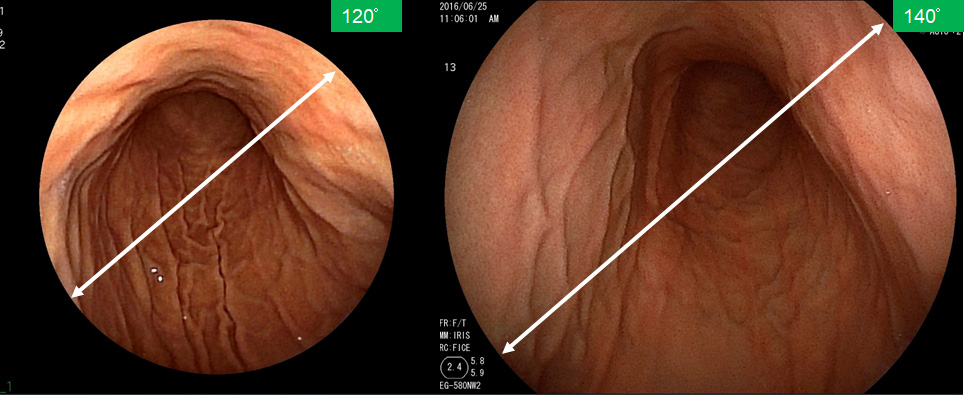

より大きく見え、画面も明るく

レーザー内視鏡の視野角は従来の内視鏡よりも広く、胃の中をより大きく映し出すことができます。また、レーザー光源を搭載していますので、画面も明るく高解像度で見やすくなっております。